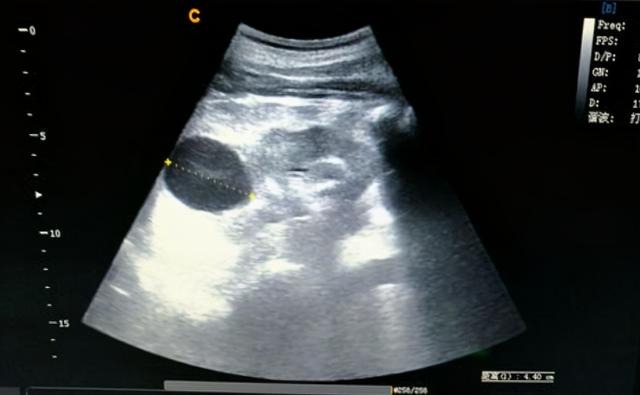

发现肾囊肿,该怎么办?需要手术治疗吗?

B超下肾囊肿典型表现为液性暗区